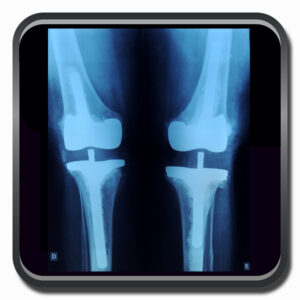

Algumas Cirurgias Complexas realizadas por profissionais da COFIB: